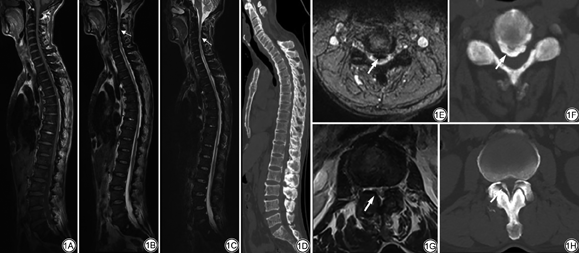

35例患者椎体内脂肪含量均减少,T1WI及T2WI信号强度表现为均匀或不均匀的不同程度减低,均伴有不同程度的骨质增生,其中颈椎间盘突出28例(80.00%)、胸椎间盘突出18例(51.43%)、腰椎间盘突出29例(82.86%)。硬膜囊前后径小于10 mm认为是椎管的绝对狭窄。椎管狭窄30例(85.71%),脊髓受压27例(77.14%),脊髓受压伴有T2WI高信号16例(45.71%),脊髓受压伴有T1WI低信号8例(22.86%)(图1A~1D)。

OPLL、OLF增厚表现为压迫硬膜囊或脊髓的不规则条状影,T1WI呈低或中等信号,T2WI呈低信号(图1E~1H)。后纵韧带正常表现为椎体后方线状稍低信号影,边缘光滑,厚度小于2 mm。OPLL分为两型:(1)连续型,OPLL连续2个椎体以上,即骨化的后纵韧带跨越椎间盘平面;(2)节段型,仅限于单个椎体后缘[6]。骨化增厚的后纵韧带厚度为4~9(6.89±2.23)mm,以颈椎最明显,均表现为连续型增厚,胸椎及腰椎后纵韧带多为节段性增厚。OPLL增厚的脊椎节段共216个,其中C2~T1有158个脊椎节段(73.15%),T1~L1有42个(19.44%),L1~S1有16个(7.41%)。颈段OPLL增厚的发生率明显高于胸段及腰段(表1)。颈段OPLL增厚以C4~C6平面最多见,C2~C7平面OPLL增厚均伴有相应层面椎管狭窄,且脊髓T2WI信号增高的发生率高于T1WI低信号(表2)。

黄韧带正常厚度为2~4 mm。骨化增厚的黄韧带厚度为4~8(5.25±1.44)mm。35个病例中,单发病变7例,多发病变21例,共计108个病变分布于C4~L5平面,其中59个病变分布于T8~T12平面,占总数的54.63%。胸段及腰段OLF增厚的发生率明显高于颈段(表1)。